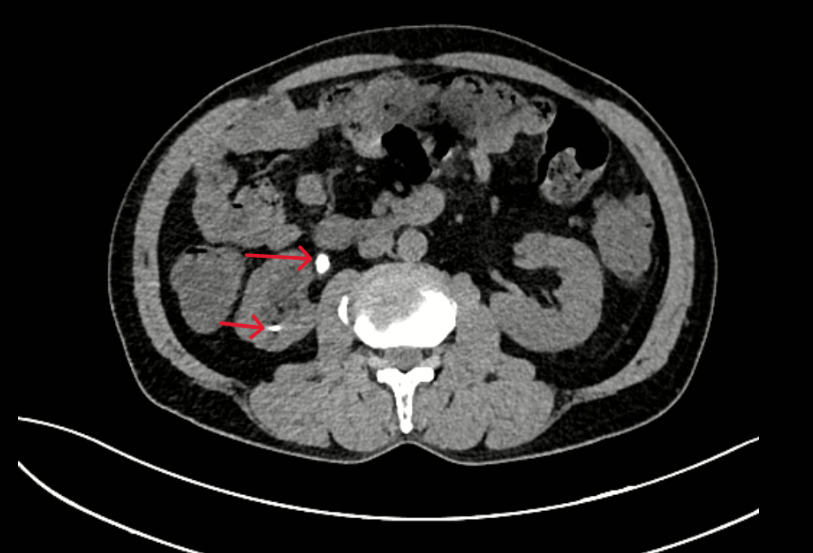

- Chụp CT bụng: Hình ảnh giãn đài bể thận và niệu quản phải do sỏi niệu quản đoạn 1/3 trên. Sỏi đài dưới thận phải.

Hình 2: Thận phải: Hình dạng và kích thước bình thường, nhu mô có nang 32mm. Đài bể thận giãn đường kính trước sau 15mm, đài dưới có sỏi kích thước 5mm. Niệu quản đoạn 1/3 trên giãn đường kính 9mm, có sỏi kích thước 7x13mm.